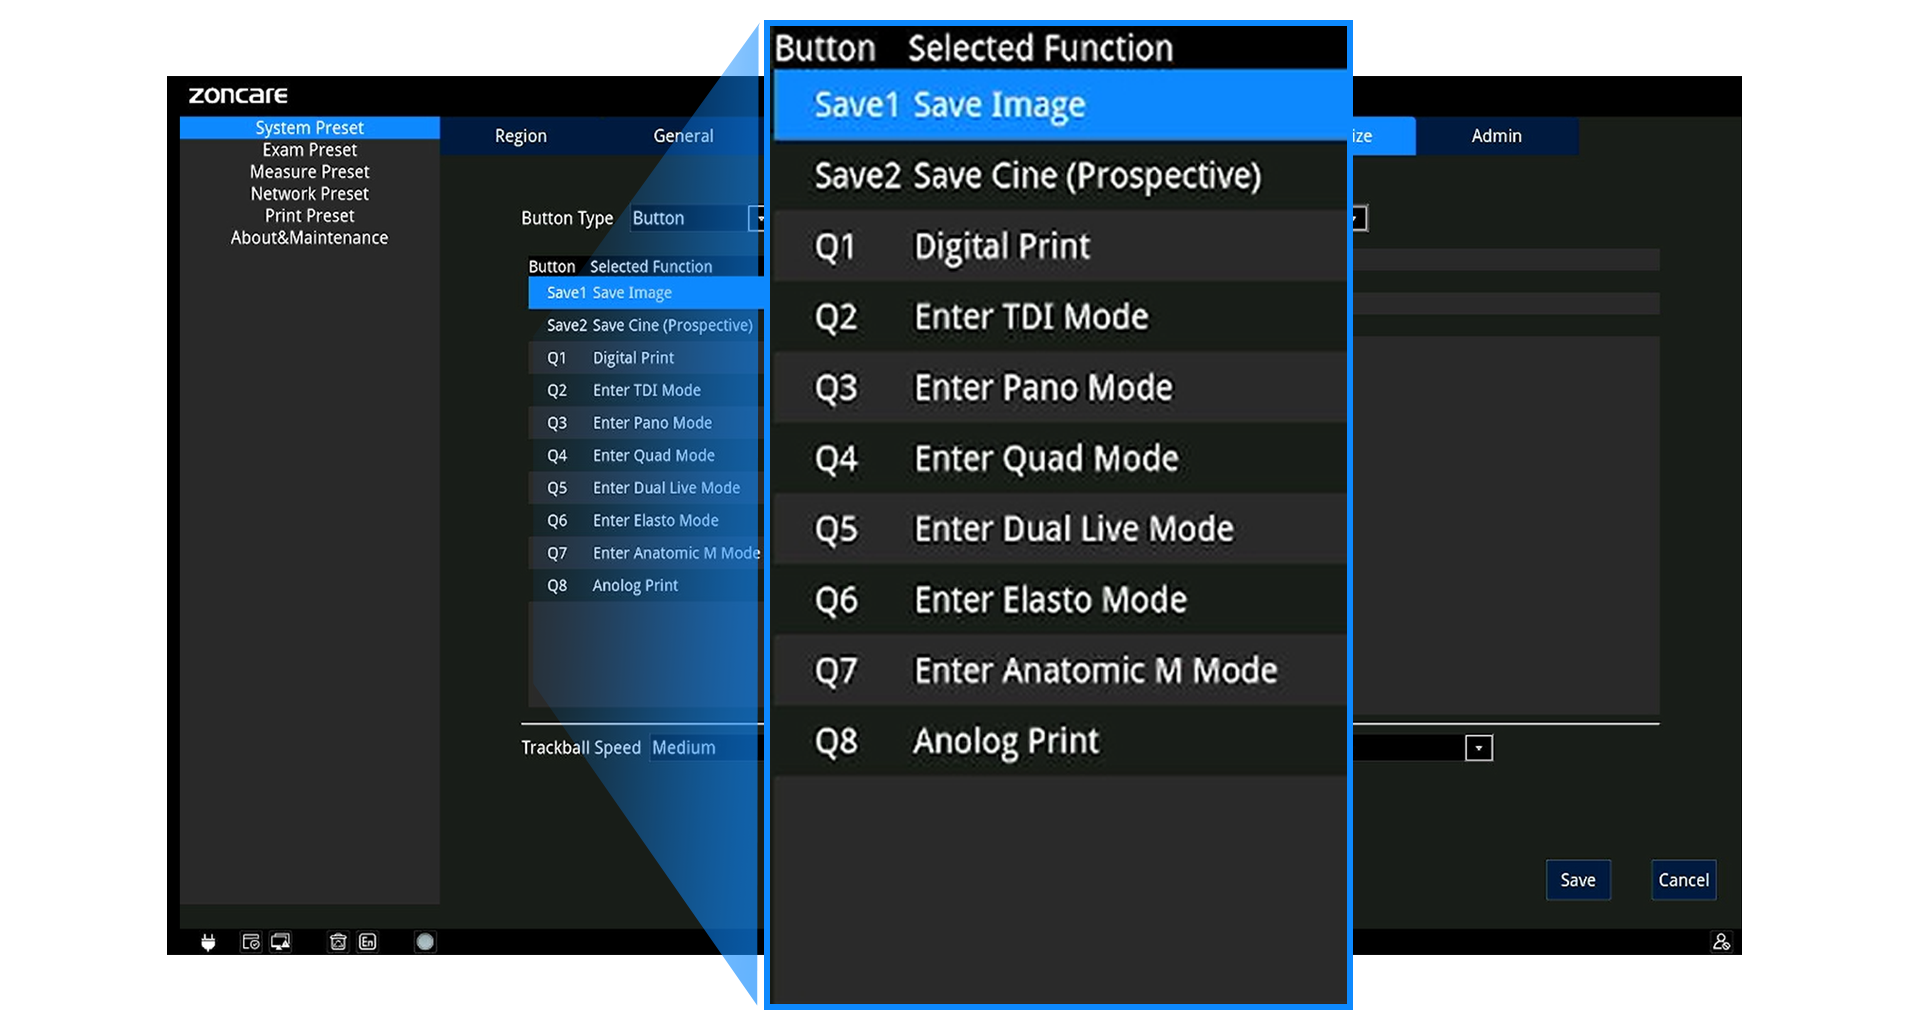

Pantalla y Operación

-

Monitor 15,6” Full HD (1920×1080)

-

Inclinación 0–75°

-

Panel ergonómico con trackball, TGC de 8 segmentos y teclas programables (Q1–Q4)

-

Arranque rápido ~75 s / Apagado ~10 s